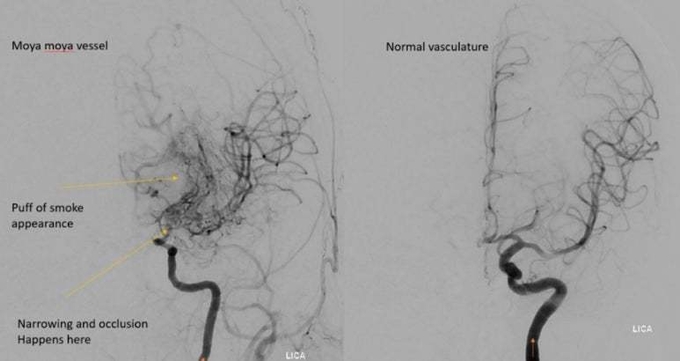

모야모야병은 뇌혈류를 공급하는 뇌 기저부 혈관이 점차 좁아지며 막히는 희귀 난치성 뇌혈관질환이다. 뇌졸중을 유발할 수 있는 질환이다.

이때 막힌 혈류를 보상하기 위해 아주 가늘고 비정상적인 새로운 혈관들이 생기는데, 이 모습이 연기(모야모야)가 피어오르는 것처럼 보여 ‘모야모야병’(moyamoya disease)이라는 일본어에서 이름이 붙었다.

진단은 뇌 MRA나 뇌 CT·MRI 등으로 하며 필요한 경우 뇌혈관조영술로 알 수 있다.